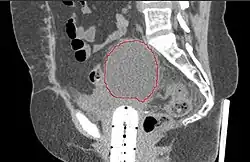

A CT scan of post-operative lymphocele

A lymphocele is a collection of lymphatic fluid within the body not bordered by epithelial lining.[1] It is usually a surgical complication seen after extensive pelvic surgery (such as cancer surgery) and is most commonly found in the retroperitoneal space. Spontaneous development is rare.[2]